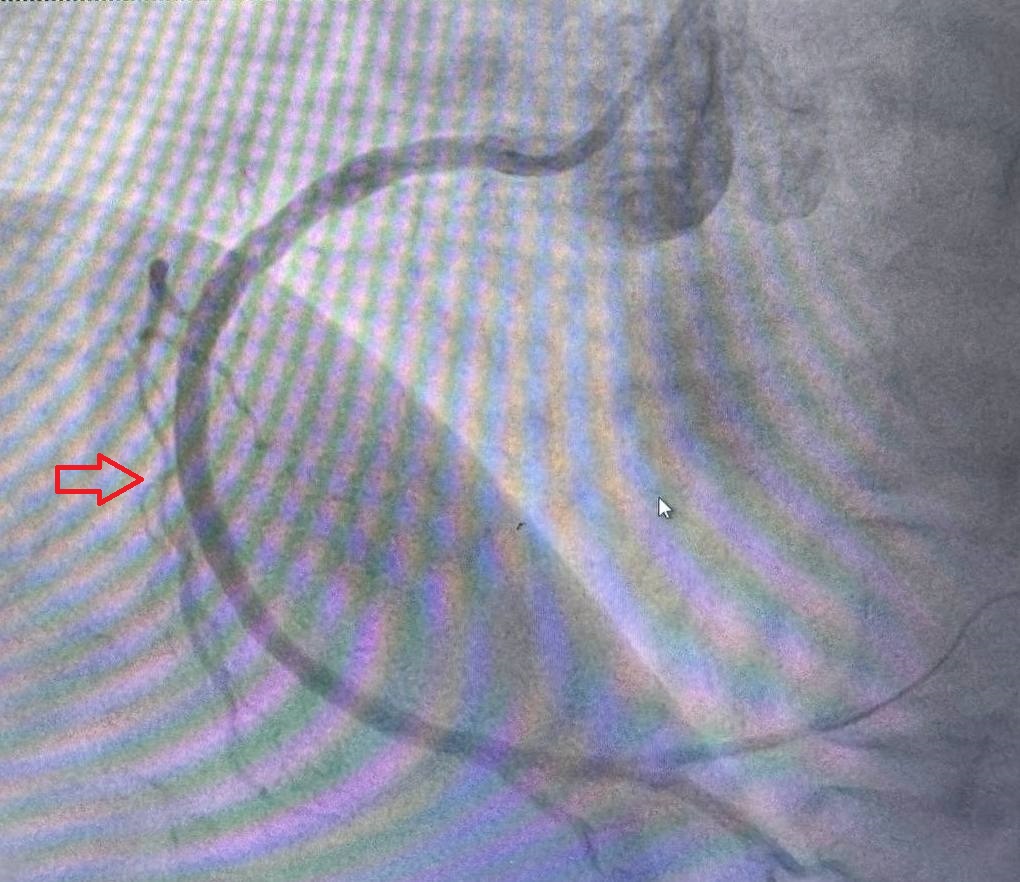

The primary endpoint was the incidence of restenosis at 12 months, assessed by coronary angiography. Restenosis was defined as ≥50% diameter stenosis in any coronary artery segment at the site of the stent. Angiography was performed in two projections both before implantation and after 12 months, using the same angle to ensure consistency.Secondary Outcomes

One-Year Follow-UpCoronary Angiography Results

Of the 60 patients who received colchicine (0.5mg daily), restenosis was observed in 4 patients (6.7%).

In the placebo group, restenosis was observedin 11 out of 60 patients (18.3%).

The use of colchicine (0.5 mg daily) significantly reduced the rate of restenosis compared to the placebo group, with a statistically significant p-value of 0.02. This result is consistent with recent meta-analyses showing that colchicine’s anti-inflammatory properties can help reduce vascular inflammation, a key factor in restenosis and other cardiovascular events.The ESC (European Society of Cardiology) and ACC (American College of Cardiology) guidelines recommend anti-inflammatory therapies for improving outcomes in patients with atherosclerotic cardiovascular disease (ASCVD). Colchicine’s role in reducing inflammation following PCI aligns with these recommendations, particularly for high-risk populations, such as patients with diabetes and vascular calcification.In the colchicine group, the restenosis rate was significantly lower across all vascular territories, with no restenosis in LAD and LCX, and a minimal rate in RCA. These results are in line with the COLCOT (Colchicine Cardiovascular Outcomes Trial) and other large studies, which demonstrated that colchicine reduces major adverse cardiovascular events (MACE) and improves long-term outcomes.Patients with vascular calcification, traditionally at higher risk for restenosis, experienced considerable benefit from colchicine therapy. This finding supports the ESC Guidelines for the Management of Chronic Coronary Syndromes, which emphasize personalized treatment strategies targeting inflammation in high-risk patients. In contrast, the placebo group showed a higher rate of restenosis, especially in vessels with significant calcification and among diabetic patients, consistent with ACC/AHA guidelines highlighting increased restenosis risk in these subgroups.These findings suggest that colchicine could be a valuable adjunctive therapy in PCI to reduce restenosis, particularly for patients at high risk of adverse outcomes. Future studies with larger cohorts are needed to confirm these results and optimize patient selection for colchicine therapy.